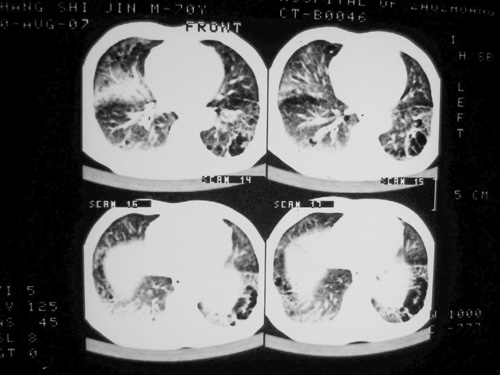

老年男性,70岁。煤矿工人20年。一周前咳嗽、发烧,拍x片考虑矽肺可能。始终咳嗽行ct检查,发现弥漫性病变,似感染但密度很高,细支气管肺泡癌无法排除,请老师给予指点。

一般矽肺多为双肺融合状,团块状高密度结节影.并散在多处小结节影.可这个病人只表现在单肺,并没有融合结节影.一周前的x片没显示大片高密度影,可定位扫描时(图象忽略传了),右肺已经清晰显示大片高密度影.作比较感觉是新病灶.可实际表现又不象,所以才拿来让各位老师看看.

矽肺,两肺间实质炎症,蜂窝肺。

矽肺  两肺间质性炎症伴纤维化(蜂窝肺)

患者病程较短,有明显咳嗽发热症状,结合病史考虑矽肺合并以间质为主的肺感染,肺泡癌先放下,抗炎再说

ct片与平片只相隔1周时间变化太大,结合临床应该首先考虑尘肺合并感染,肺泡癌变化不会这么快,